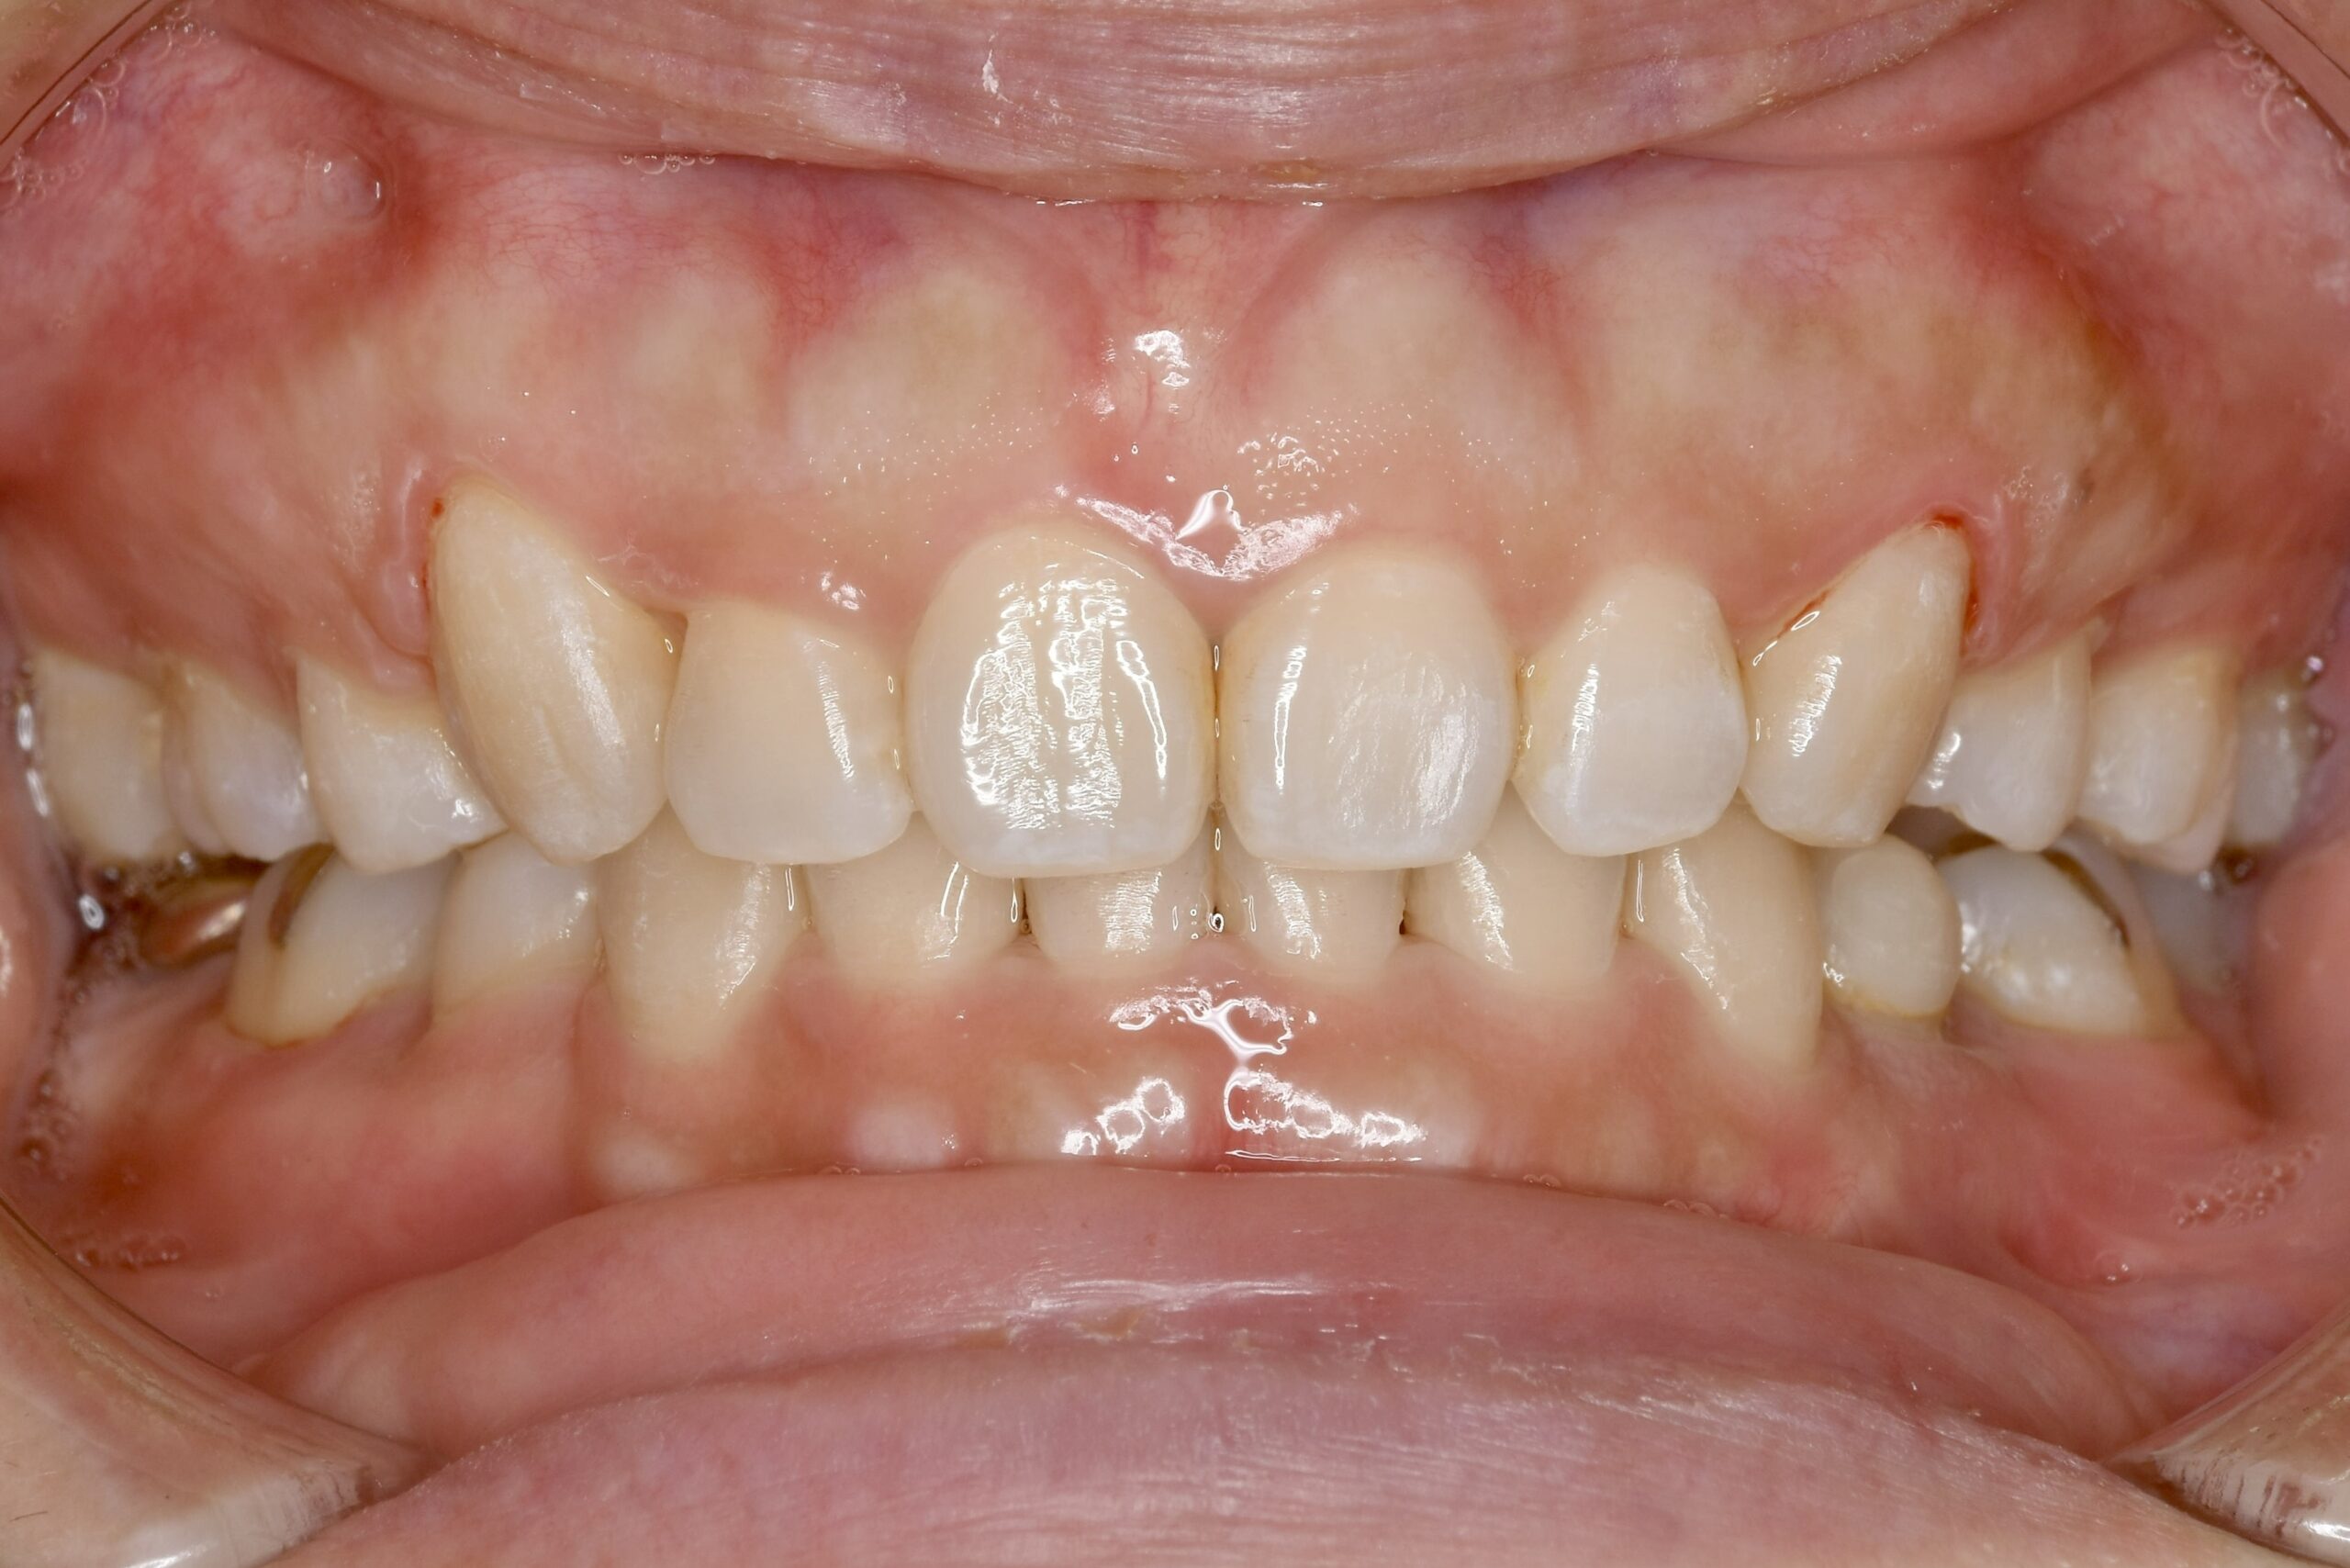

乳歯と永久歯が混在する時期に行う矯正歯科治療です。

顎や口腔機能の成長・発育といった「土台」から正しい歯並びへ導く、お子様ならではの矯正治療が行えます。

負担を考えた、お子様一人ひとりに適切な装置を使用します。

永久歯が生え揃ってから行う矯正歯科治療です。

患者様それぞれのご希望を叶えられるよう、難症例にも対応できる装置はもちろん、治療中の見た目を気にされている方も安心できる、透明で目立たないマウスピース型矯正装置もご用意しております。